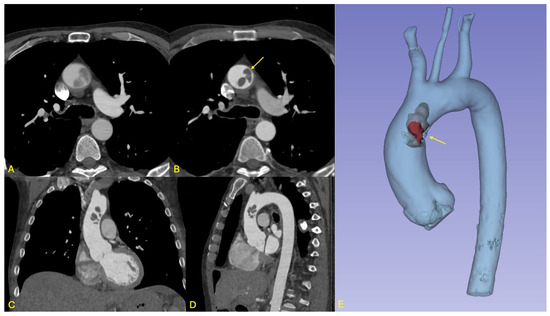

Figure 1. Overview of imaging findings in patient 1. (A,B): Respective axial views from the non-gated and ECG-gated CT angiographies performed at initial imaging work-up showing the impact of ECG-gating on thrombus visualization and contours. (A,B) Lobulated endoluminal structure with no apparent contact with the aorta is visualized on this slice (arrow in B). (C,D): Coronal and sagittal views of the ECG-gated CT angiography showing the cranio-caudal extension of this thrombotic formation. (E): 3D multi-planar reconstruction showing the significance of the thrombus with respect to the aortic lumen, and the attachment to the left aspect of the ascending aorta (arrow). No other thrombi were identified.